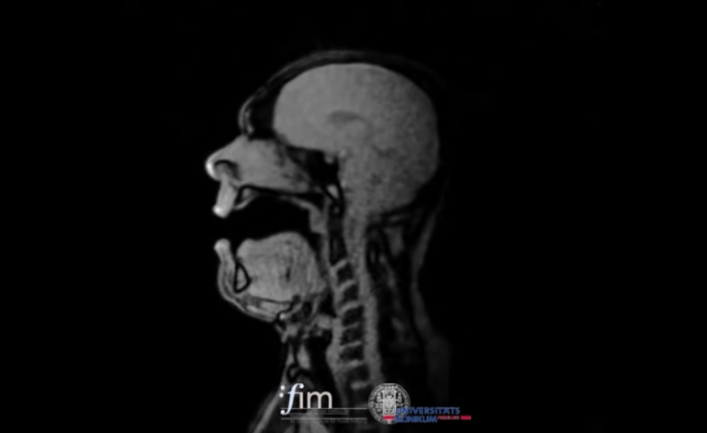

Esto es lo que se ha propuesto un grupo de investigación del Centro Médico de la Universidad de Friburgo en Alemania, donde varios científicos convocaron a 12 cantantes profesionales en diferentes clasificaciones de voz para analizar sus proceso de canto dentro de una máquina de imágenes por resonancia magnética, registrando en tiempo real el proceso de canto. El video que han compartido de uno de los participantes es alucinante. Escuchemos:

El cantante es el barítono Michael Volle, interpretando “Oh Du, mein holder Abendstern” de la opera “Tannhäuser” de Richard Wagner. En la muestra se logran ver la cantidad de procesos inteligentes que se articulan, los cuales representan el interés central de los científicos, quienes buscaban averiguar la relación entre la dependencia de la articulación con respecto al volumen del canto. Para ello pedían a los músicos cantar a diferentes escalas ascendentes en tres condiciones de volumen, para luego analizar la frecuencia fundamental y el nivel de presión.

Según cuentan sus resultados, se aprecian notables diferencias de articulación con respecto a los cambios de pitch y volumen, por ejemplo en la apertura de los labios, la posición de la laringe o el ensanchamiento de la faringe. Por ejemplo, al cantar la vocal “a”,se mostraba un efecto radical en la articulación fisiológica, entre otros resultados y conclusiones que sin duda son importantes tanto para los conocimientos de la medicina como para el enriquecimiento de los procesos de técnica vocal, el entendimiento de los cantantes con respecto a su cuerpo y la mejora de determinadas situaciones físicas.